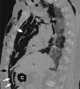

Pneumomediastinum with abdominal extension of air

Pneumatosis intestinalis